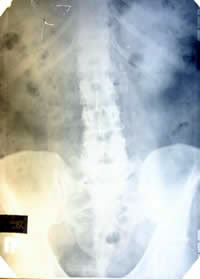

Обследование

по поводу отдаленных метастазов |

|